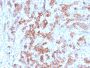

PC3, BT474, HepG2, HDLM-2 or Daudi cells. Tonsil, lymph node or spleen.

IHC, FFPE (verified)

IHC (FFPE) (verified)